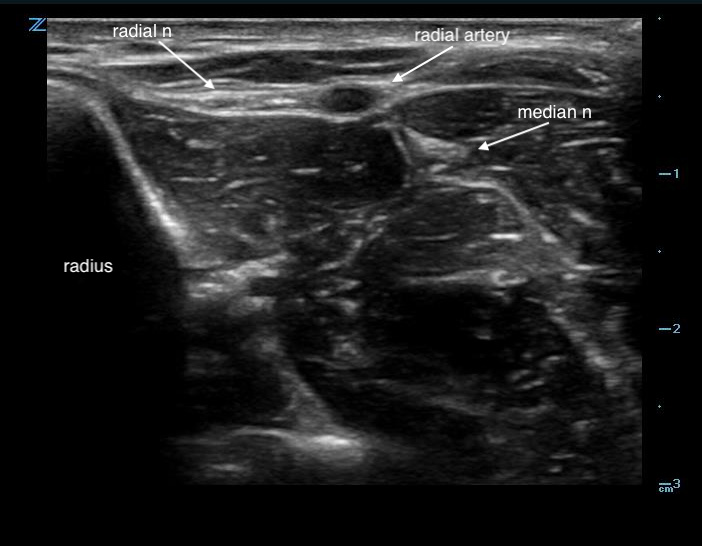

Figure 1. Sonographic appearance of the radial nerve in the mid-forearm

- Place the probe transversely on the volar surface of the forearm.

- Slide the probe laterally to identify the pulsatile radial artery.

- Directly lateral to the radial artery should be a hyperechoic structure representing the radial nerve.

- The nerve can be oval or triangular.

- The radial nerve sits in the same echogenic fascial plane as the artery.

- If not immediately seen, rapidly slide up and down the radial artery from the mid-forearm to identify the nerve associating with the artery.